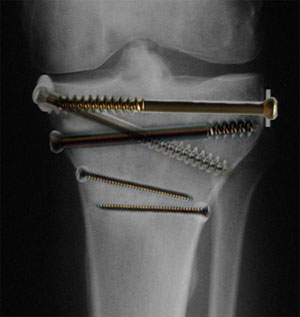

...lieber das linke: Prof. Leutenegger und Dr. Zwetkow (Merci auch für die schönen Träume während der Narkose, Herr Liesch) drehten in kurzer Zeit einige schöne Schrauben aus dem Knie - wie hatten sie die am 16. April bloss da rein gebracht?!

...wobei die eine so ausgeleiert war, dass man sich lieber nicht vorstellt, was da während der Narkose so alles passiert sein muss. (Frage dazu von J. aus B.: "Das sind ja mega Dinger! Die sind jetzt draussen, aber wurden die im Hirn auch wirklich richtig angezogen?" - Pahh! - In einem Punkt muss ich J. aber recht geben: "Wie wär's, wenn du Samuel Stutz bald ablösen würdest mit deinen Erfahrungsberichten?")

Jedenfalls darf nun wieder fröhlich gehinkt (und frühestens Mitte Dezember wieder Ski gefahren) werden: Die Schrauben sind zwar draussen, aber die Streckung des Beins hat vorerst nicht wieder hergestellt werden können. Die Kreuzbänder sind falsch eingewachsen, und womöglich ist ein Knochensporn im Weg - und der müsste abgehobelt werden. Das wäre frühestens nach einem MRI oder CT im kommenden Winter möglich, bedeutet aber unweigerlich eine weitere Operation mit längerer Rekonvaleszenz und wieder ein paar Wochen an Krücken. "Mist" kann man das auch nennen. Machbar sei es aber laut den Chirurgen - immerhin!

Wenn man die Schrauben rausnehmen kann, kann man sie doch sicher einfach wieder reinschrauben...?

Grössere Fassung